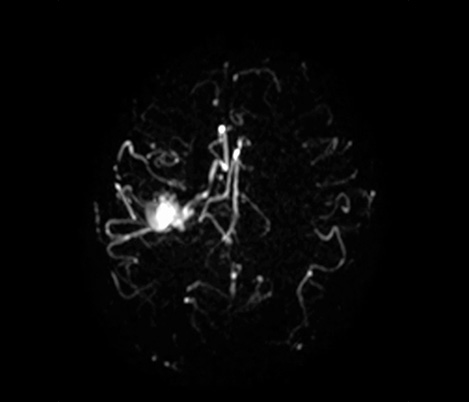

At the Rothschild Foundation Hospital in Paris we run most of our post contrast T1 TSE sequences with MSDE black blood suppression because it is easier to interpret the data with the high signal from small vessels removed to optimize conspicuity of contrast enhancing lesions.

Dr. Savatovsky, Fondation Rothschild, Paris, France